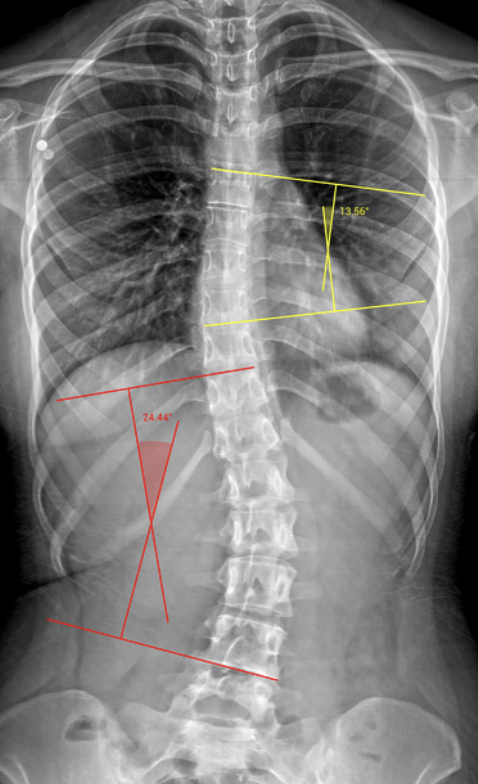

Critical Clinical Evaluation: Every assessment includes a full spinal exam and specific spinal and joint X-rays (if necessary) to evaluate for misalignments, arthritis, disc compression, or scoliosis.

Protection and Longevity: Working out with undiagnosed issues like joint arthritis or spinal curvatures can dramatically impact your health and longevity if done incorrectly. This step is critical for a healthy workout program and protects your spine and joints before you start training.

Doctor Review: You will review all tests, exams, and X-rays with the doctor so you feel confident and understand exactly what to focus on for optimal results.